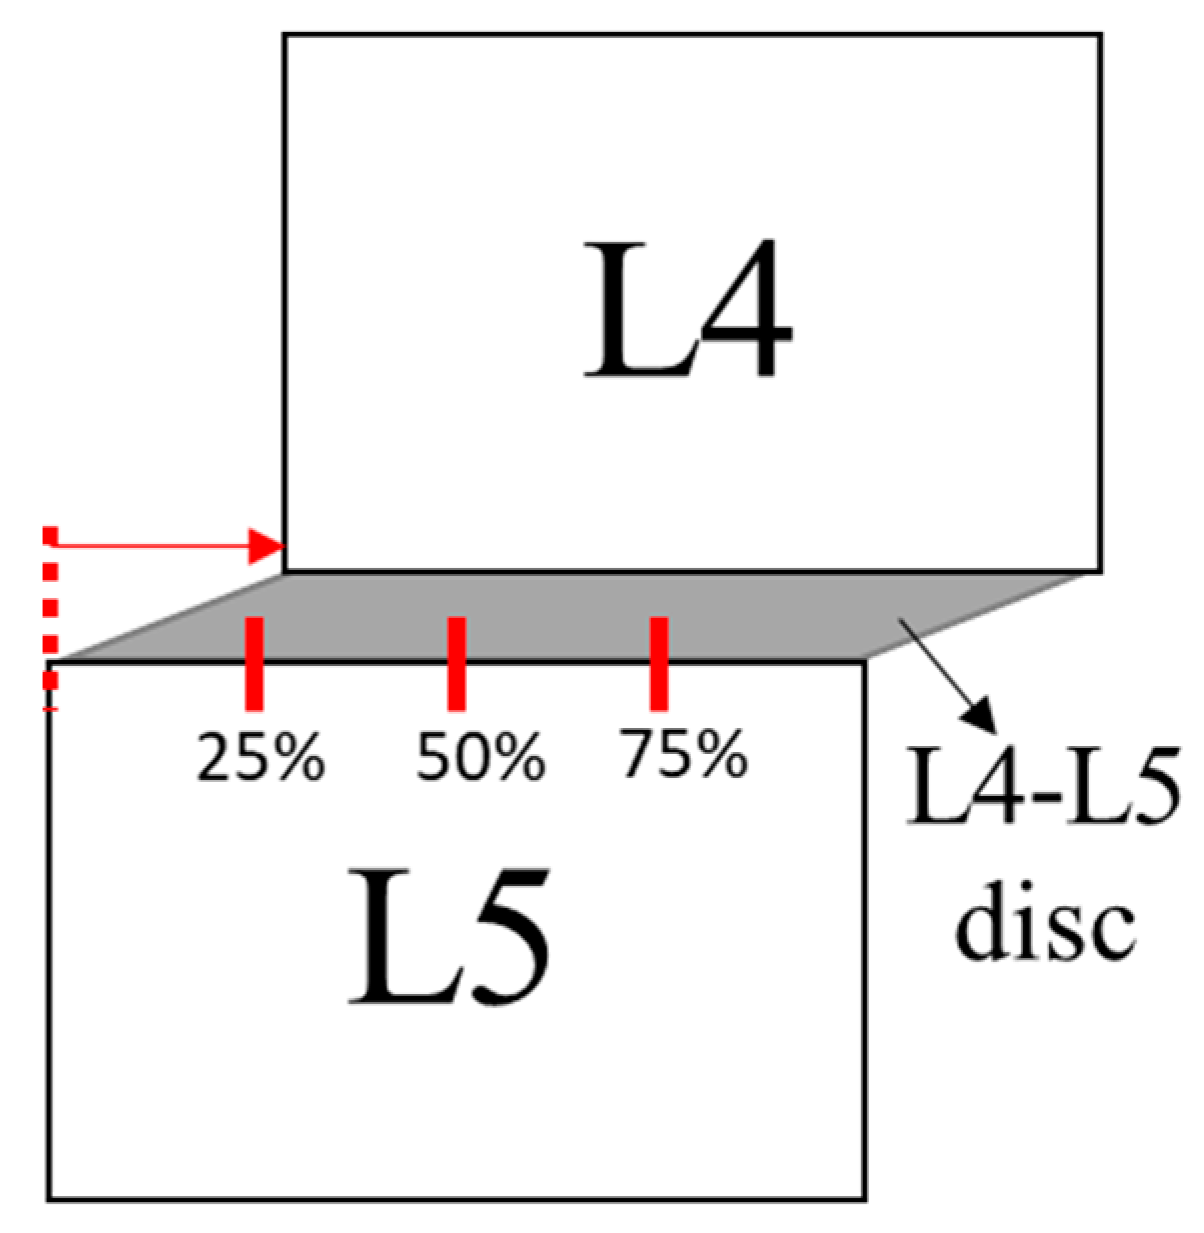

2.2.2. Spondylolisthesis

| Meyerding Classification | Percentage of Slip |

|---|---|

| Grade I | 0–25% |

| Grade II | 25–50% |

| Grade III | 50–75% |

| Grade IV | 75–100% |

| Grade V | >100% |